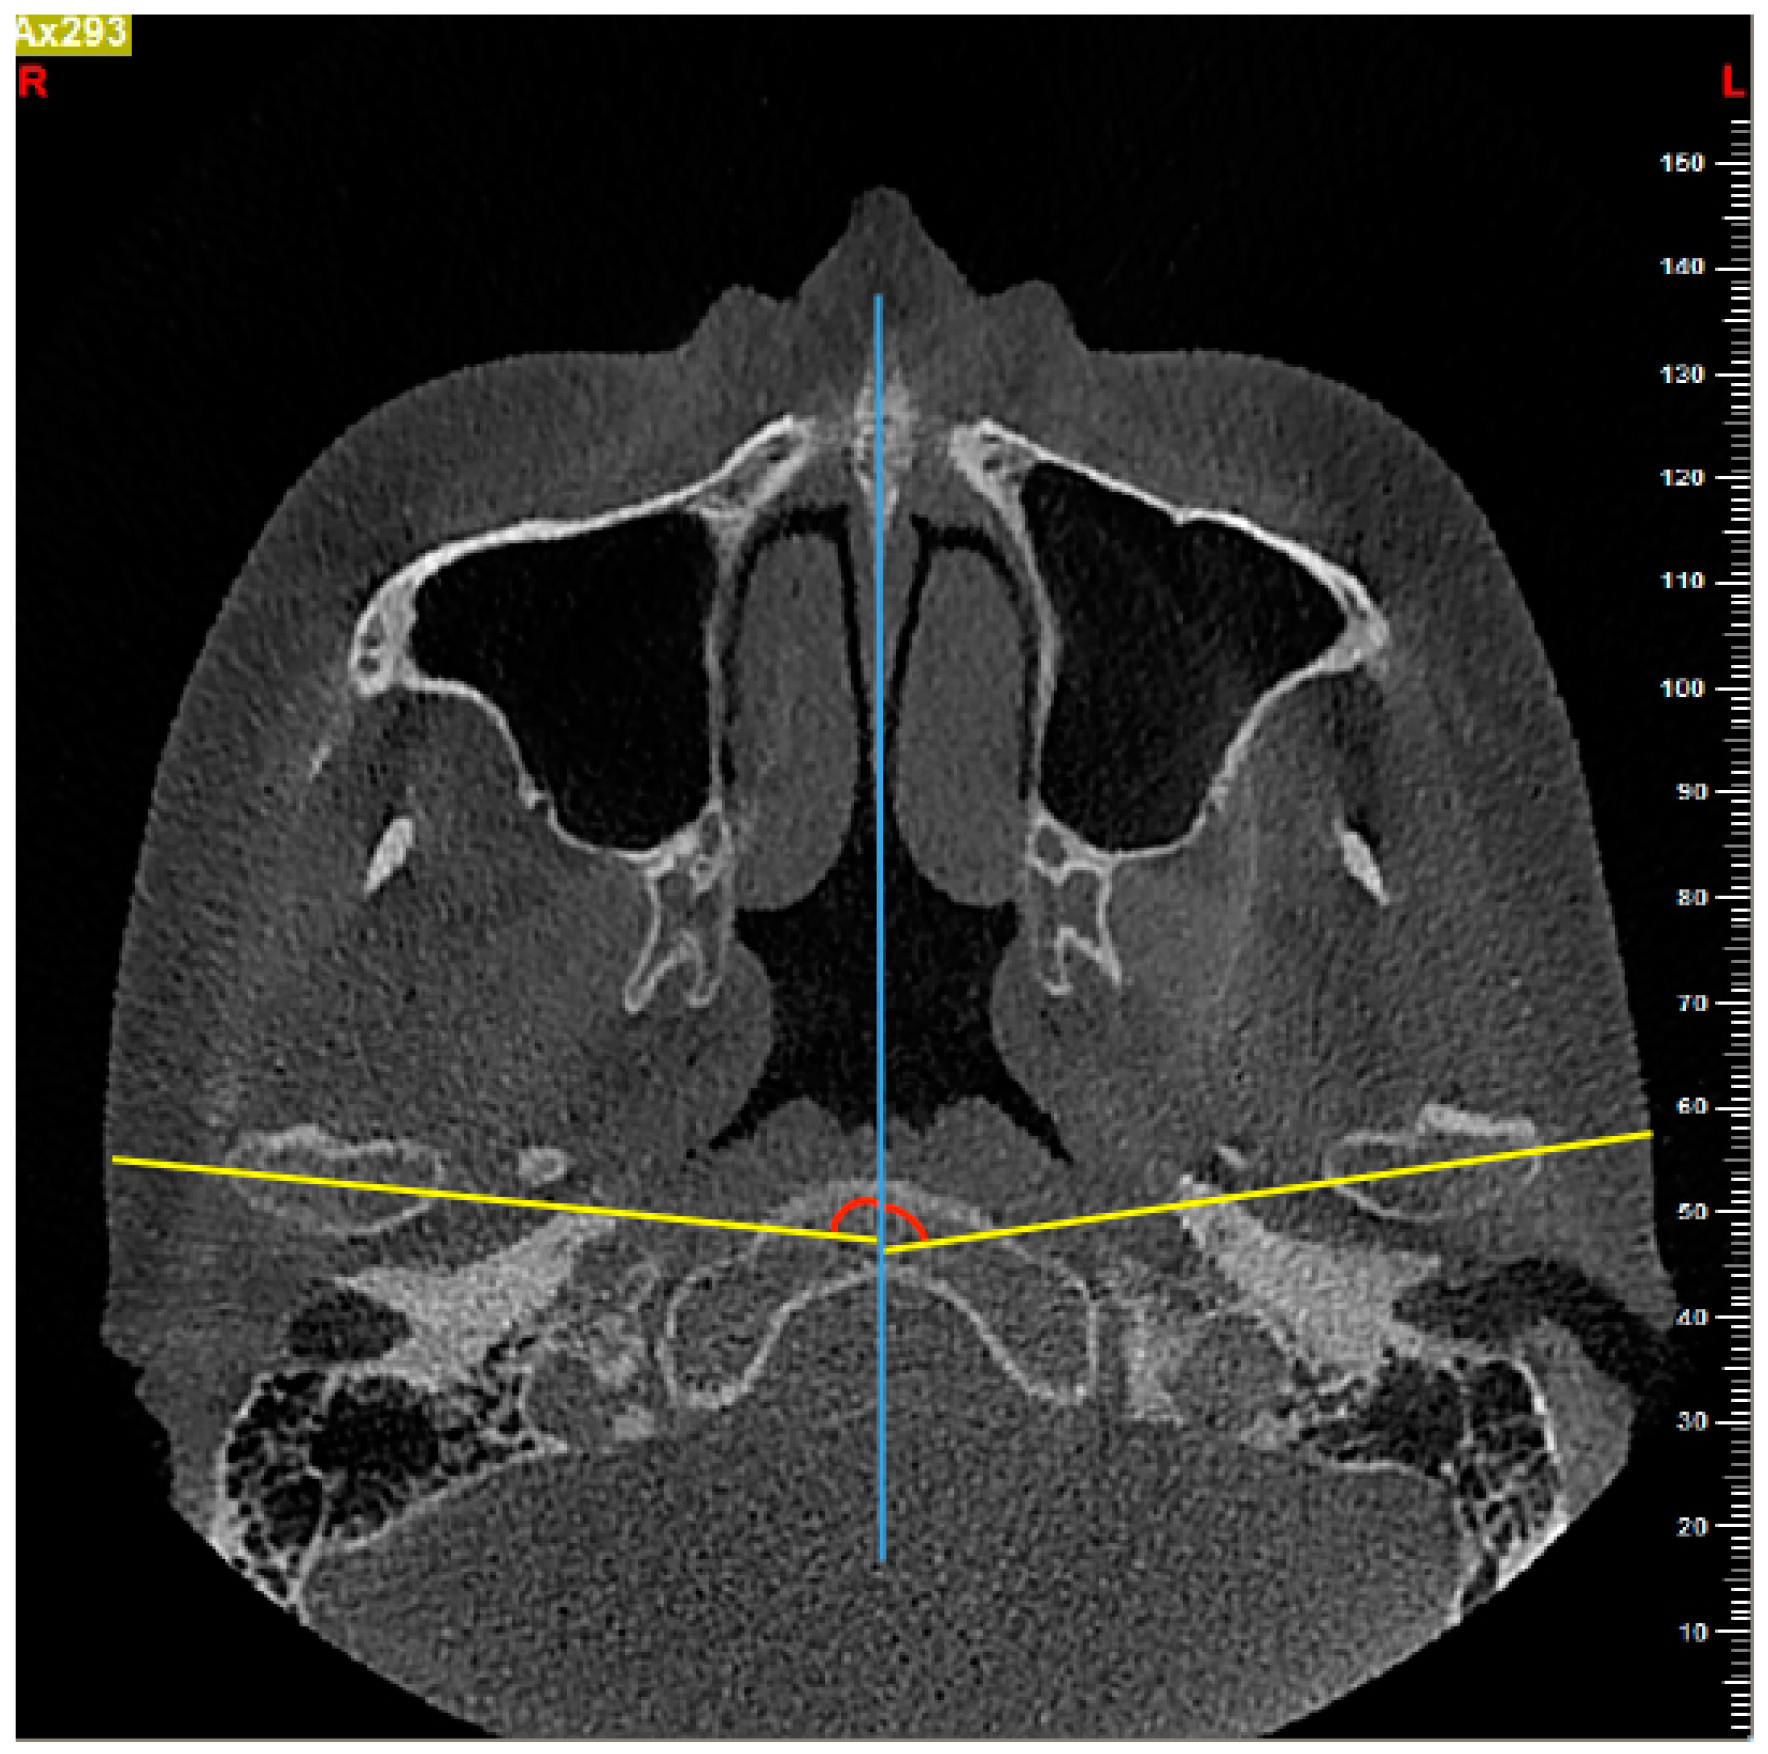

2.4. Measurements